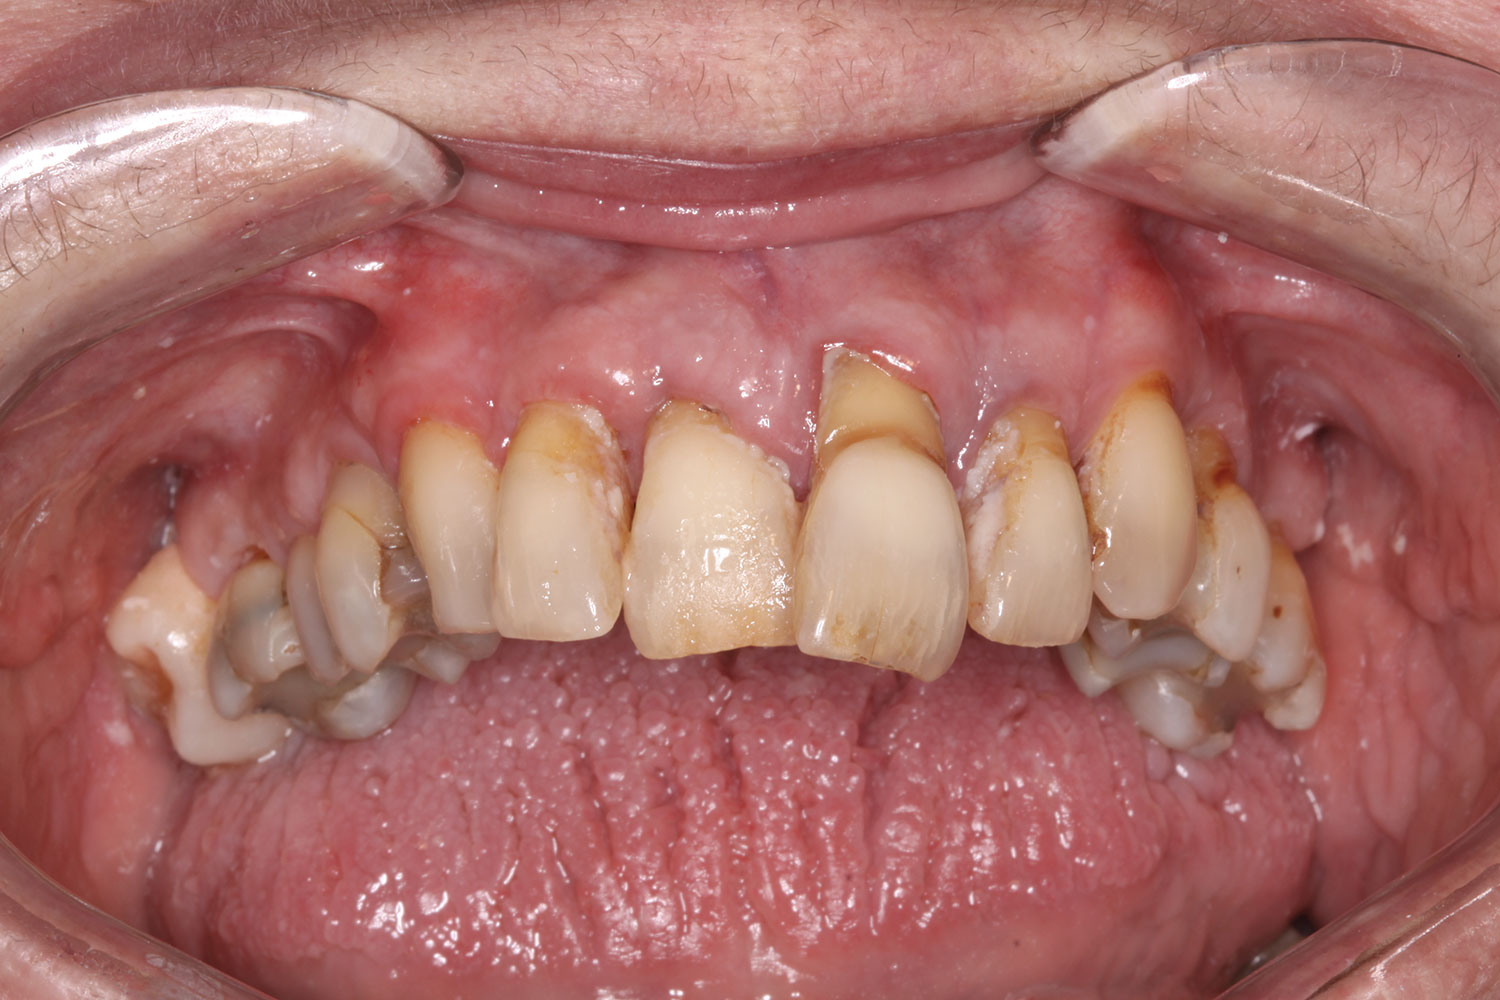

Fig 10. Initial clinical situation, intraoral view.

Figure 10

A 60-year-old female patient presented with many periodontally and restoratively hopeless teeth that severely compromised esthetics and function and were inadequate to retain a maxillary restoration. She declined to advance into a full maxillary denture or partial denture. Existing maxillary teeth included Nos. 2 and 4 through 14 (Figure 9 and Figure 10). The opposing dentition was stable. The patient was in good health with no allergies to medication.